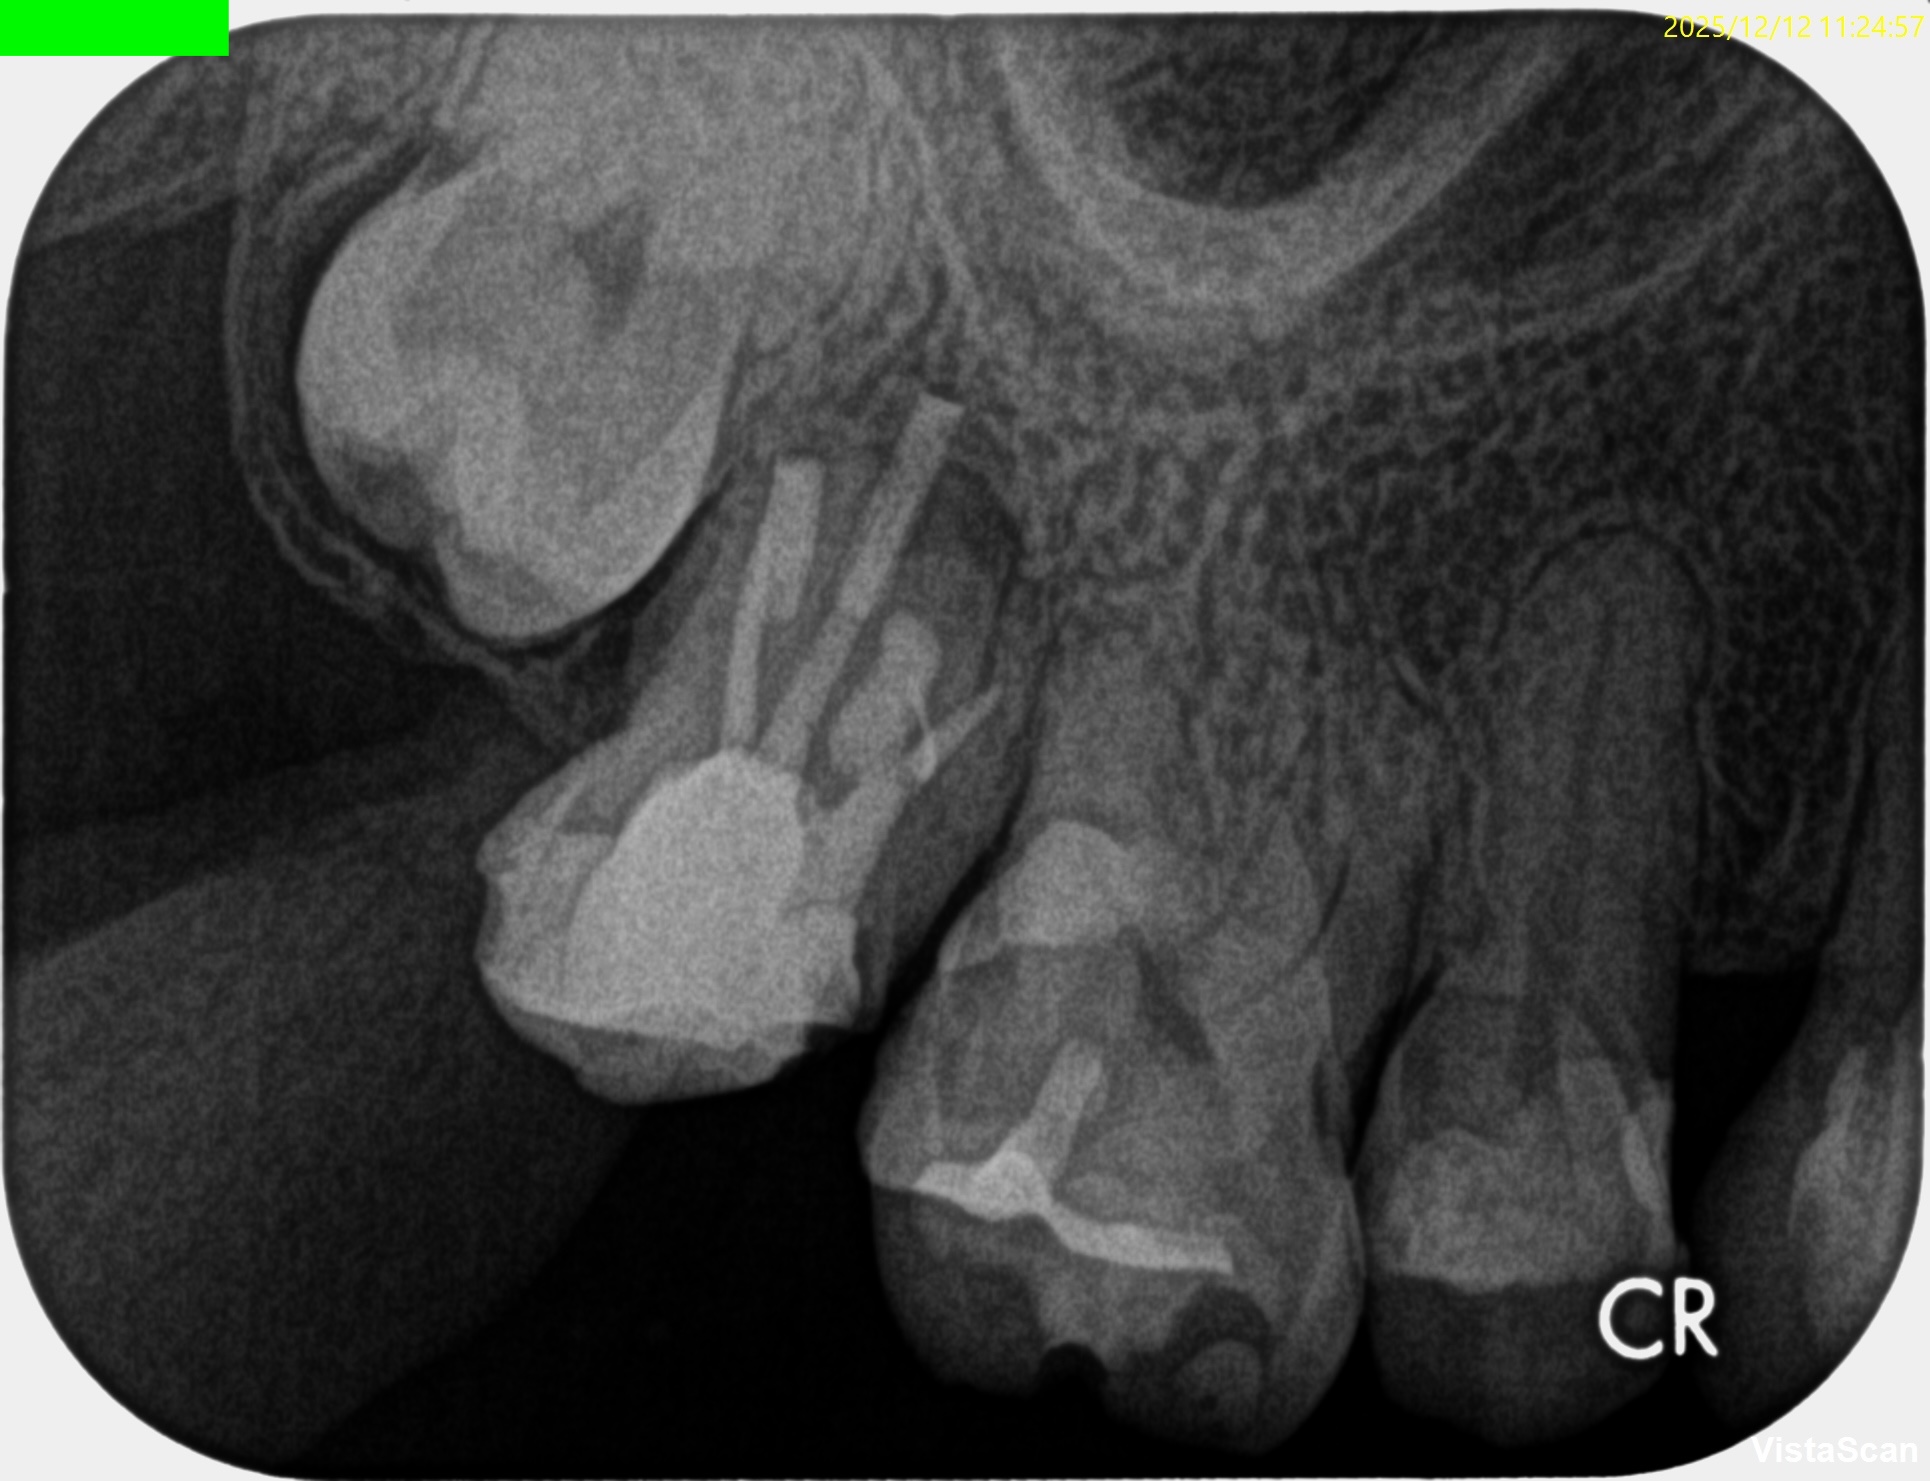

Pre-op Endo test(2025.12.12)

#2 Cold N/A, Perc.(+), Palp.(-), BT(++), Perio Probe(WNL), Mobility(WNL)

依頼された#2には咬合痛と打診痛がある。

近心根にファイルが折れ込んでいる。

MB

DB

P

Pre-op Endo Diagnosis(2025.12.12)

Pulp Dx:Previously treated

Periapical Dx:Symptomatic apical periodontitis

Recommended Tx: Intentional Replantation